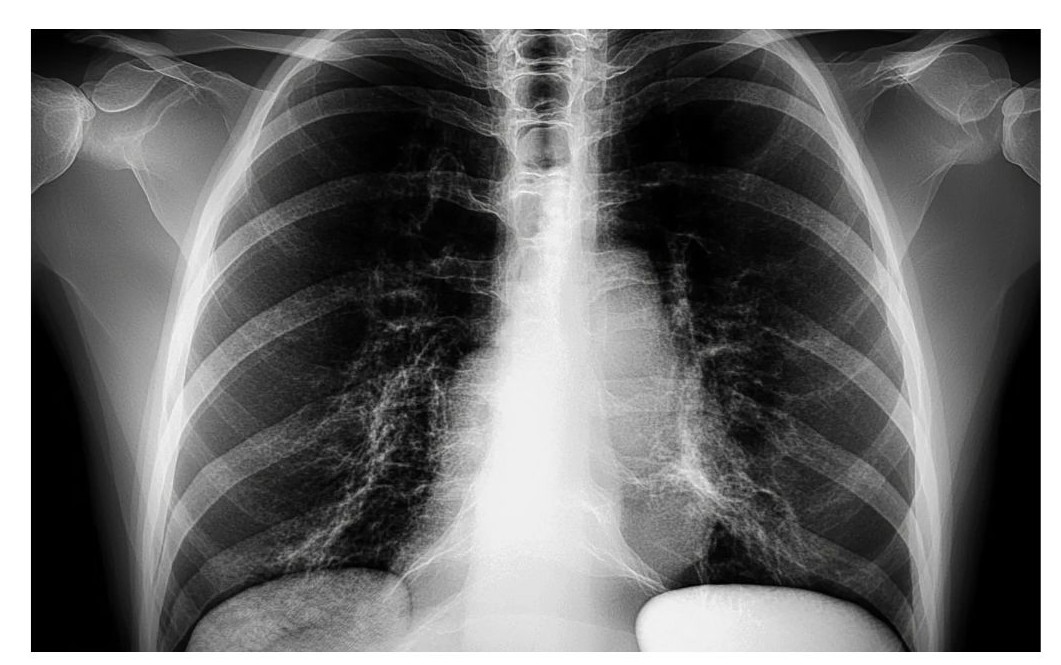

② 호흡기 문제

- 천식, 만성 기관지염, 폐렴, 폐혈전 등은 가슴이 답답하고 숨 쉬기 힘든 느낌을 줍니다.

- 체크 포인트: 깊게 숨을 들이쉴 때 통증이나 압박감, 지속적인 기침, 호흡 곤란